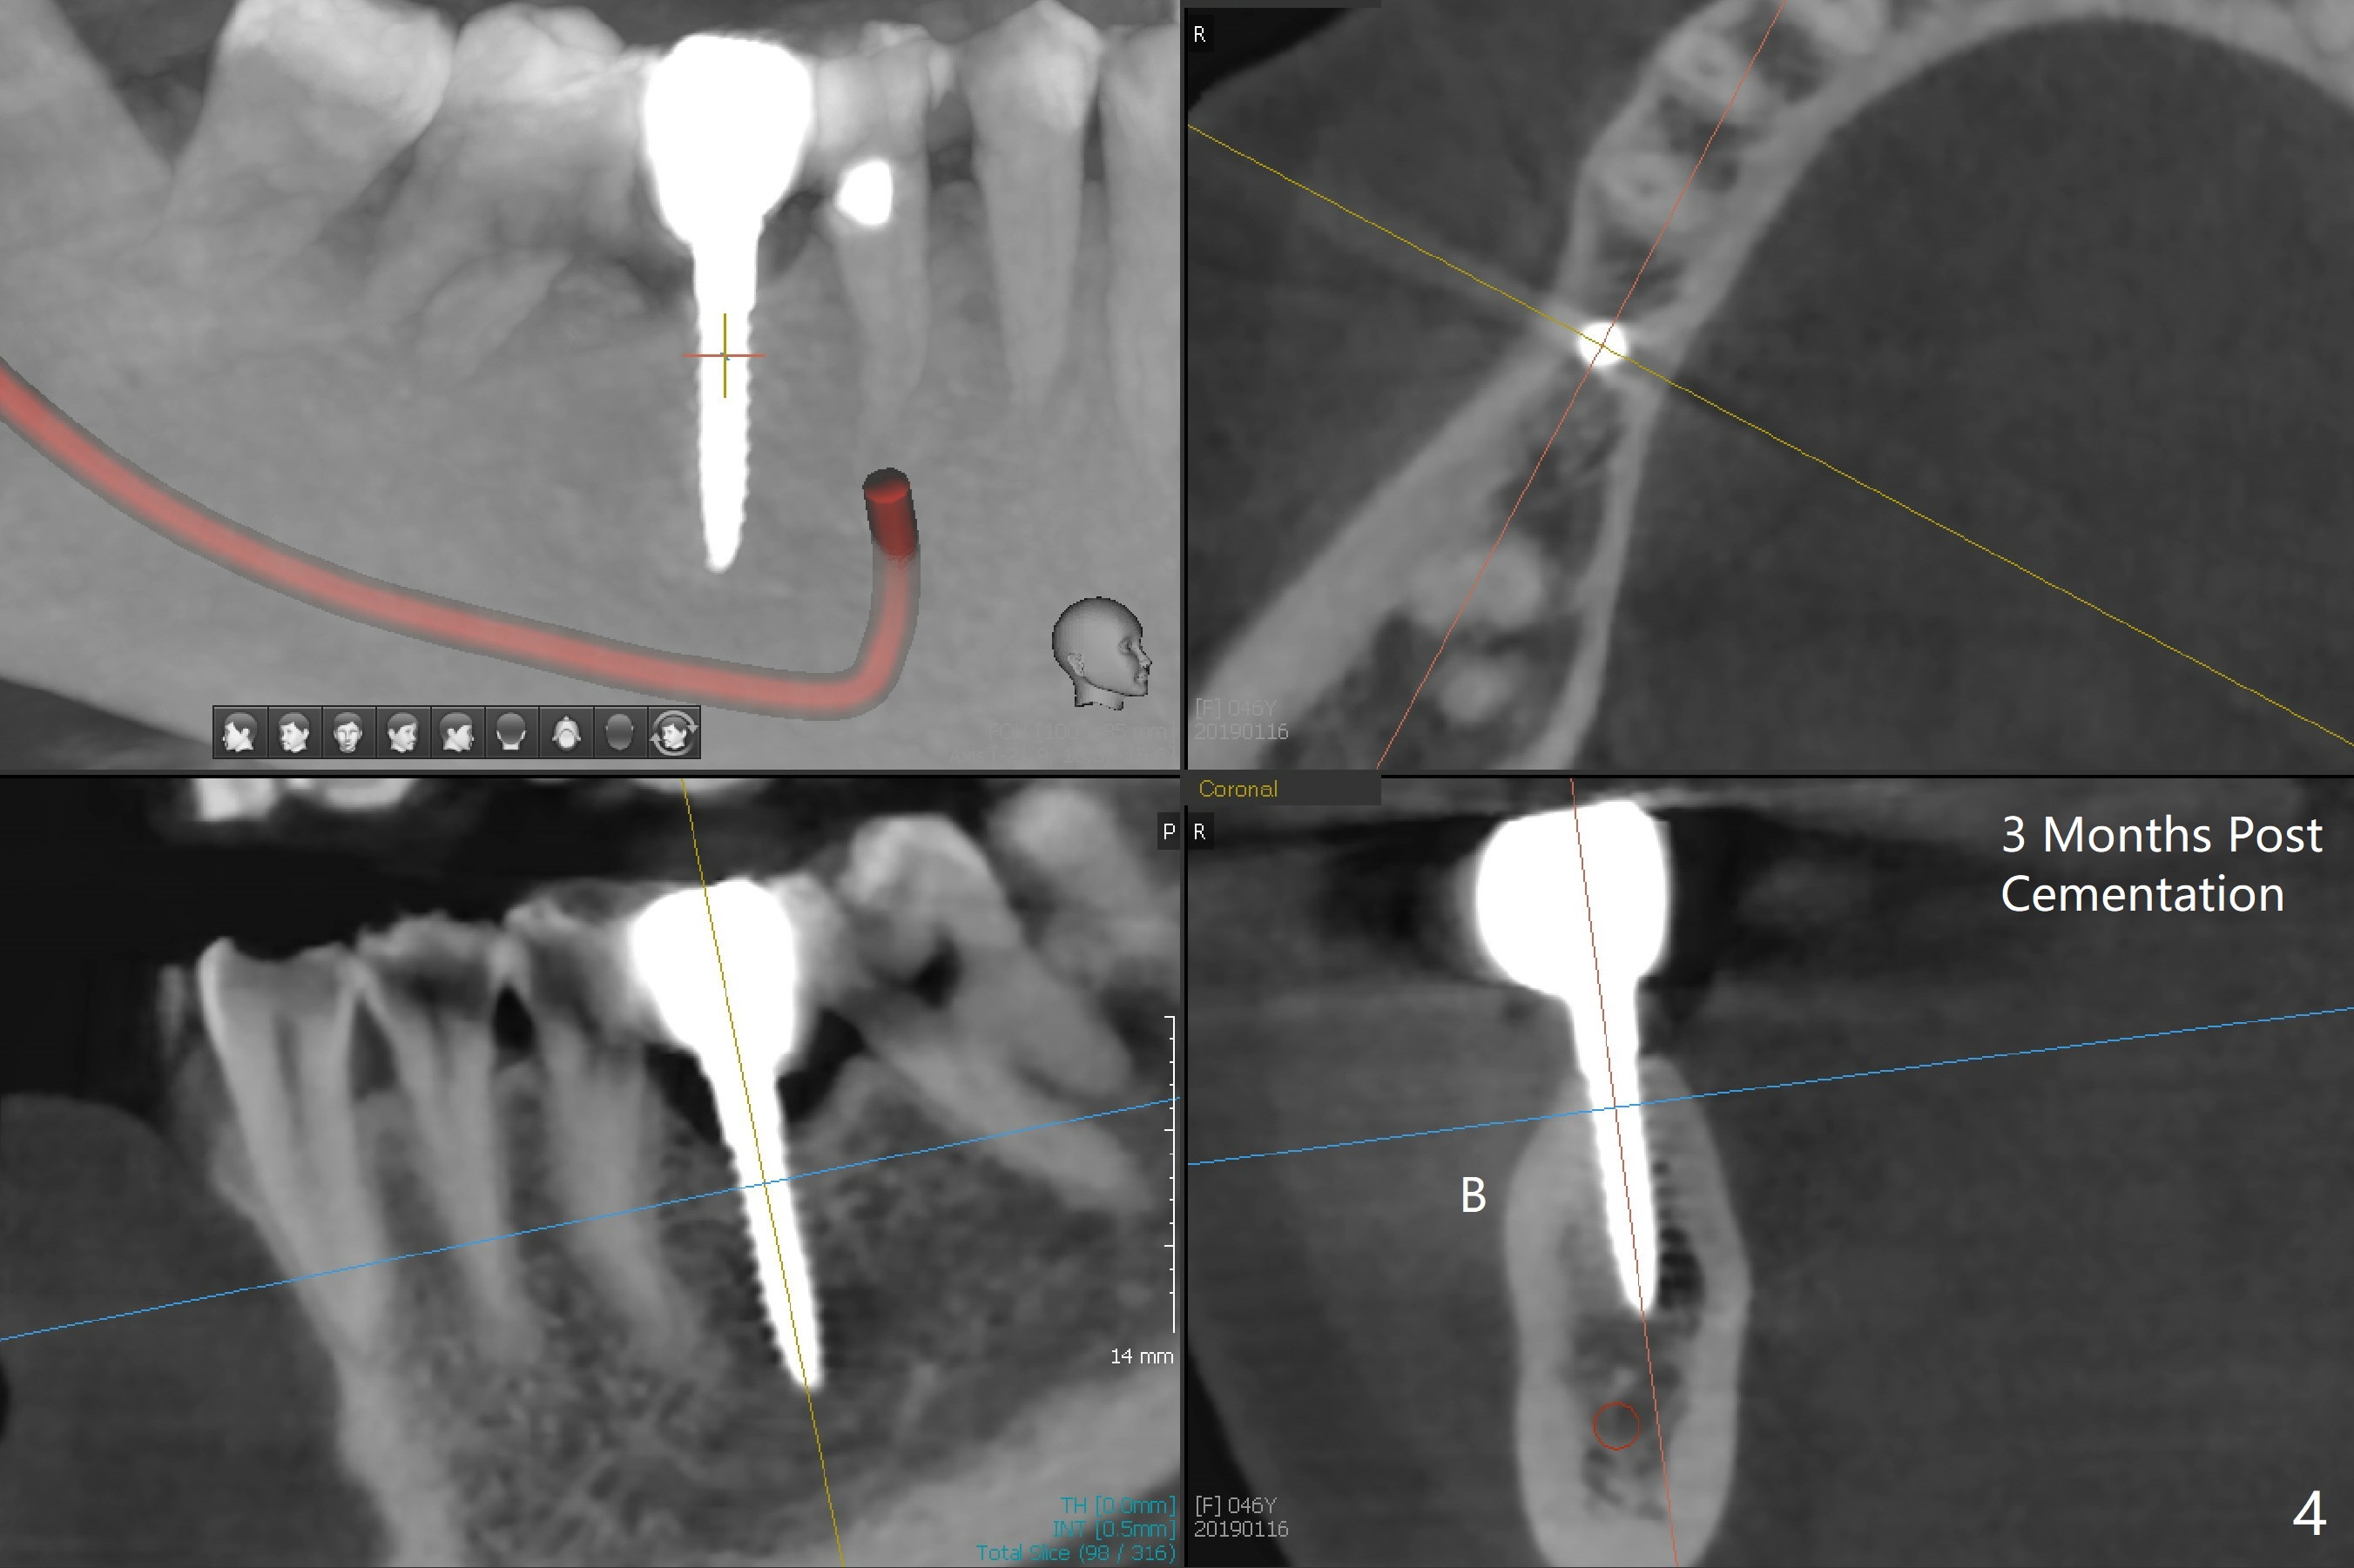

The mesial surface of the tooth #31 is reduced prior to osteotomy (Fig.1 >) so that the mesiodistal width of the edentulous area is 4.5 mm. An incision is made instead of tissue punch because of the narrow keratinized gingiva. The potential osteotomy site happens to have nonkeratinized tissue. When a 2.5x12(2) mm 1-piece implant is placed, it is close to the curved root of the 2nd premolar (Fig.2 *). Because of apparently sufficient clearance from the Inferior Alveolar Canal (Fig.2 red dashed line), the implant is placed ~ 1 mm deeper later. After suturing, periodontal dressing is applied. At patient's request, a provisional is fabricated with occlusal clearance 26 days postop. The occlusal surface of the provisional perforates 3.5 months postop with the provisional having pressed the gingiva, which is consistent with crestal bone loss (Fig.3). There appears no bone loss 3 months post cementation (Fig.4). There is minimal bone loss 11 months post cementation; in fact the bone density around the coronal portion of the implant increases (Fig.5).